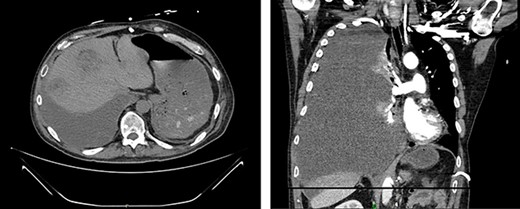

Serial CT scans at 10 and 12 weeks post-resection revealed reduction of the retroperitoneal abscess and appearance of liver lesions concerning for metastasis (Fig. 4). The patient eventually completed his radiation course with no additional problems.

First appearance of multiple liver lesions suspicious for metastasis in transverse (left) and coronal (right) planes on CT; reduction of retroperitoneal effusion can also be seen.